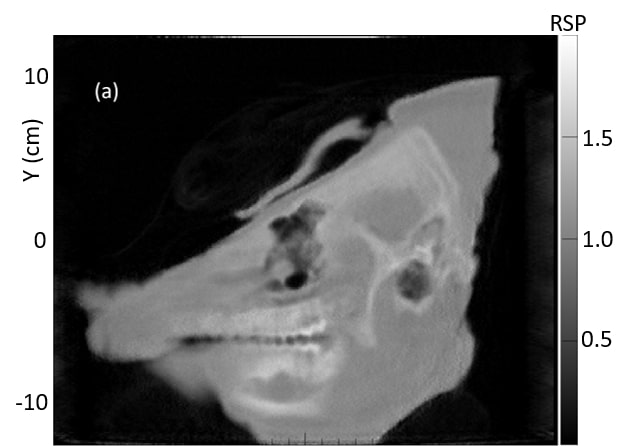

Fig. 8 shows a comparison of the average of ten 1 mm sagittal slices from a lateral region of the pig’s head for pCT and the vertical x-ray CT, in order to reduce noise. Features are slightly blurred due to their change in shape with depth. The grey scale reflects the measured RSP, whereas in Fig. 6 and 7 the grey scales were windowed and levelled to optimize contouring. The largest differences are in regions of heterogeneity such as the teeth and tympanic bullae.